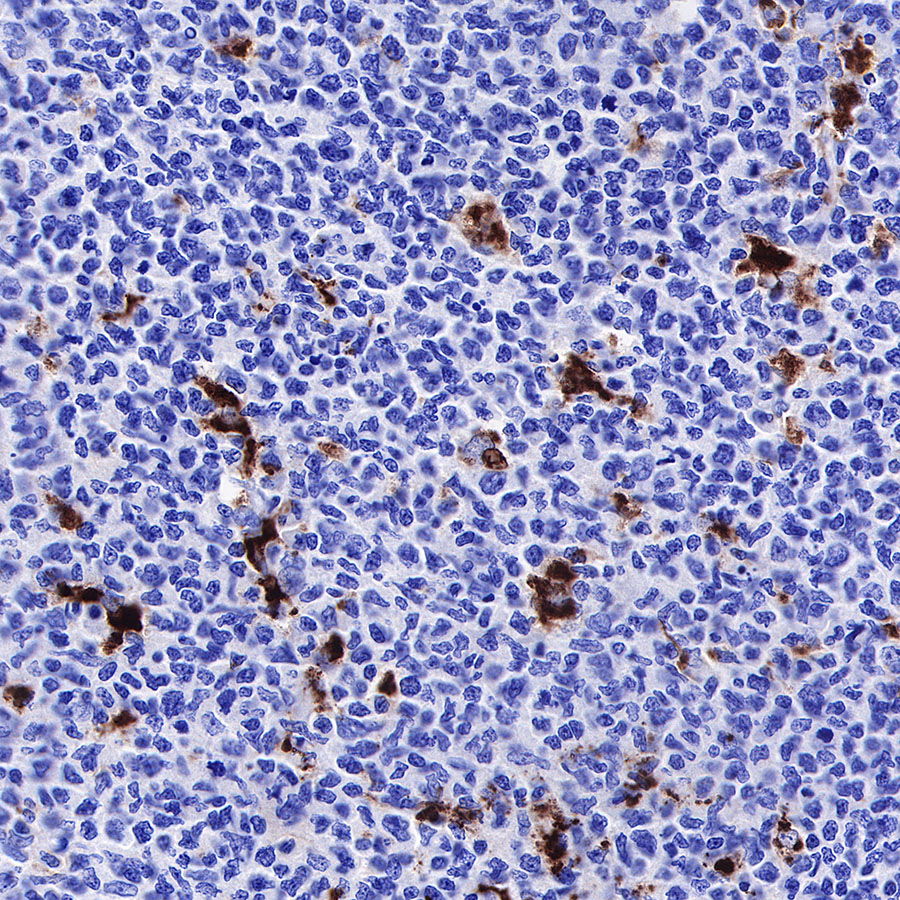

IHC shows positive staining in paraffin-embedded human diffuse large B-cell lymphoma. Anti-CD68 antibody was used at 1/1000 dilution, followed by a HRP Polymer for Mouse & Rabbit IgG (ready to use). Counterstained with hematoxylin. Heat mediated antigen retrieval with Tris/EDTA buffer pH9.0 was performed before commencing with IHC staining protocol.